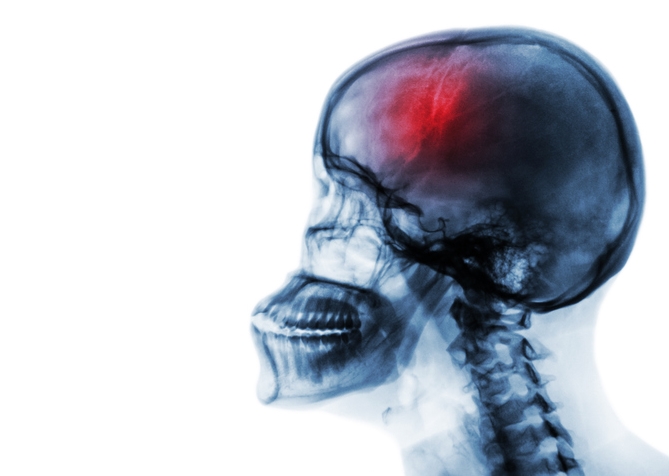

Q5. 뇌종양은 진단되기까지 시간이 오래 걸리나요?

A. 뇌종양 초기증상이 모호하고 일상적인 증상과 겹쳐 진단이 늦어지는 경우가 많습니다. 종양의 성장 속도가 느릴 경우 수개월, 수년간 증상이 드러나지 않을 수 있어요. 하지만 뇌 MRI나 CT 촬영을 통해 조기 발견이 가능하므로, 증상이 의심될 땐 진료를 미루지 마세요.